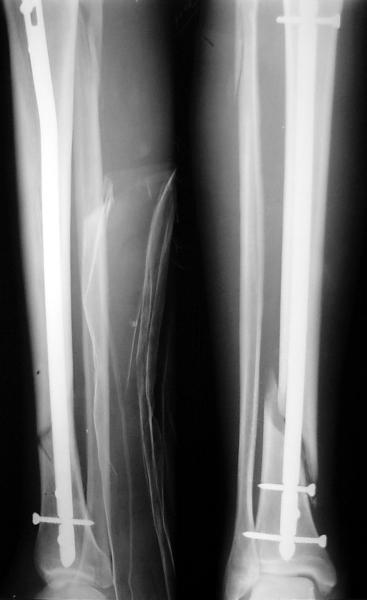

JOM> Кстати, если можно пошлите послеоперационный снимок.

Ok. А также и следующий, в 3 месяца.

JOM> Ваш больной имеет счастье, что первым согнулся проксимальный

JOM> замыкающий винт, а не дистальный и гвоздь не пенетрировал

Это не счастье, а тонкий инженерный расчет ;-))

Сверху - один статический винт, а снизу - три. Что раньше сломается? Конечно, он потом и нижние сломал, и Вы правы, если бы верхний динамичесий винт уже уперся бы в нижний край отверстия, будь гвоздь подлинее, перфорировал бы сустав как пить дать.

Как я уже говорил, мы сделали выводы из этого и других подобных случаев. Очевидно, решений проблемы два - либо уменьшить нагрузку, либо увеличить прочность фиксатора. Первое решение работает не со всеми больными, так что пошли по второму пути - мы больше не используем гвозди с запирающими винтами диаметром 4 мм.